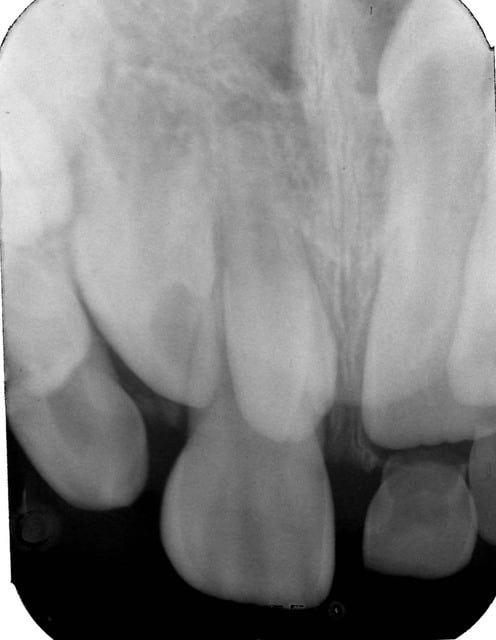

Deuxième cas , radiographies 11b et 21b ,

chez un garçon de 7 ans .

La 11 est sur l'arcade nettement vestibulée avec une mésiodens superposée .

La 21 est en normoposition, on distingue (?) en position haute une mésiodens orientée vers les fosses nasales .

TRT à voir .